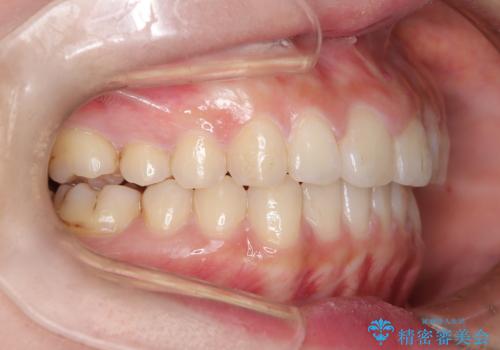

- 口元の突出感、歯のがたつきを主訴に来院された患者様です。非抜歯にて口元を下げるような治療計画を立案しました。非常に治療に対して真面目で協力的な患者様で、一緒に理想形を相談しながら治療を進めました。矯正前には、虫歯治療や親知らず抜歯を行っています。噛みしめ癖が強く、終盤は奥歯の噛み合わせのためにゴム掛けにご協力いただきました。